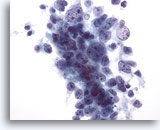

画像 4

肝FNA – 良性肝細胞

反応性変化を来した肝細胞。核は大小不同で、二核を有しています。

40倍

画像 4

肝FNA – 良性肝細胞

反応性変化を来した肝細胞。核は大小不同で、二核を有しています。

40倍